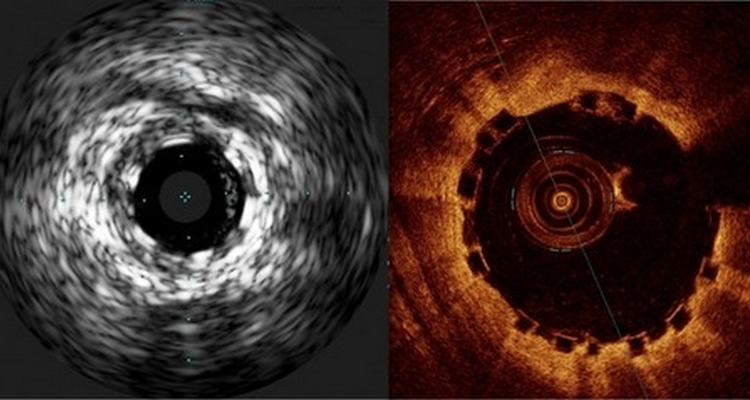

一文详解:冠状动脉扩张的诊治

在冠状动脉造影中,常常会遇到一种特殊的病变,即冠状动脉扩张。其发病机制和冠状动脉狭窄相近,但又不完全相同,在治疗策略上也有一些独特之处。下面我们就来认识一下冠状动脉扩张.临床研究